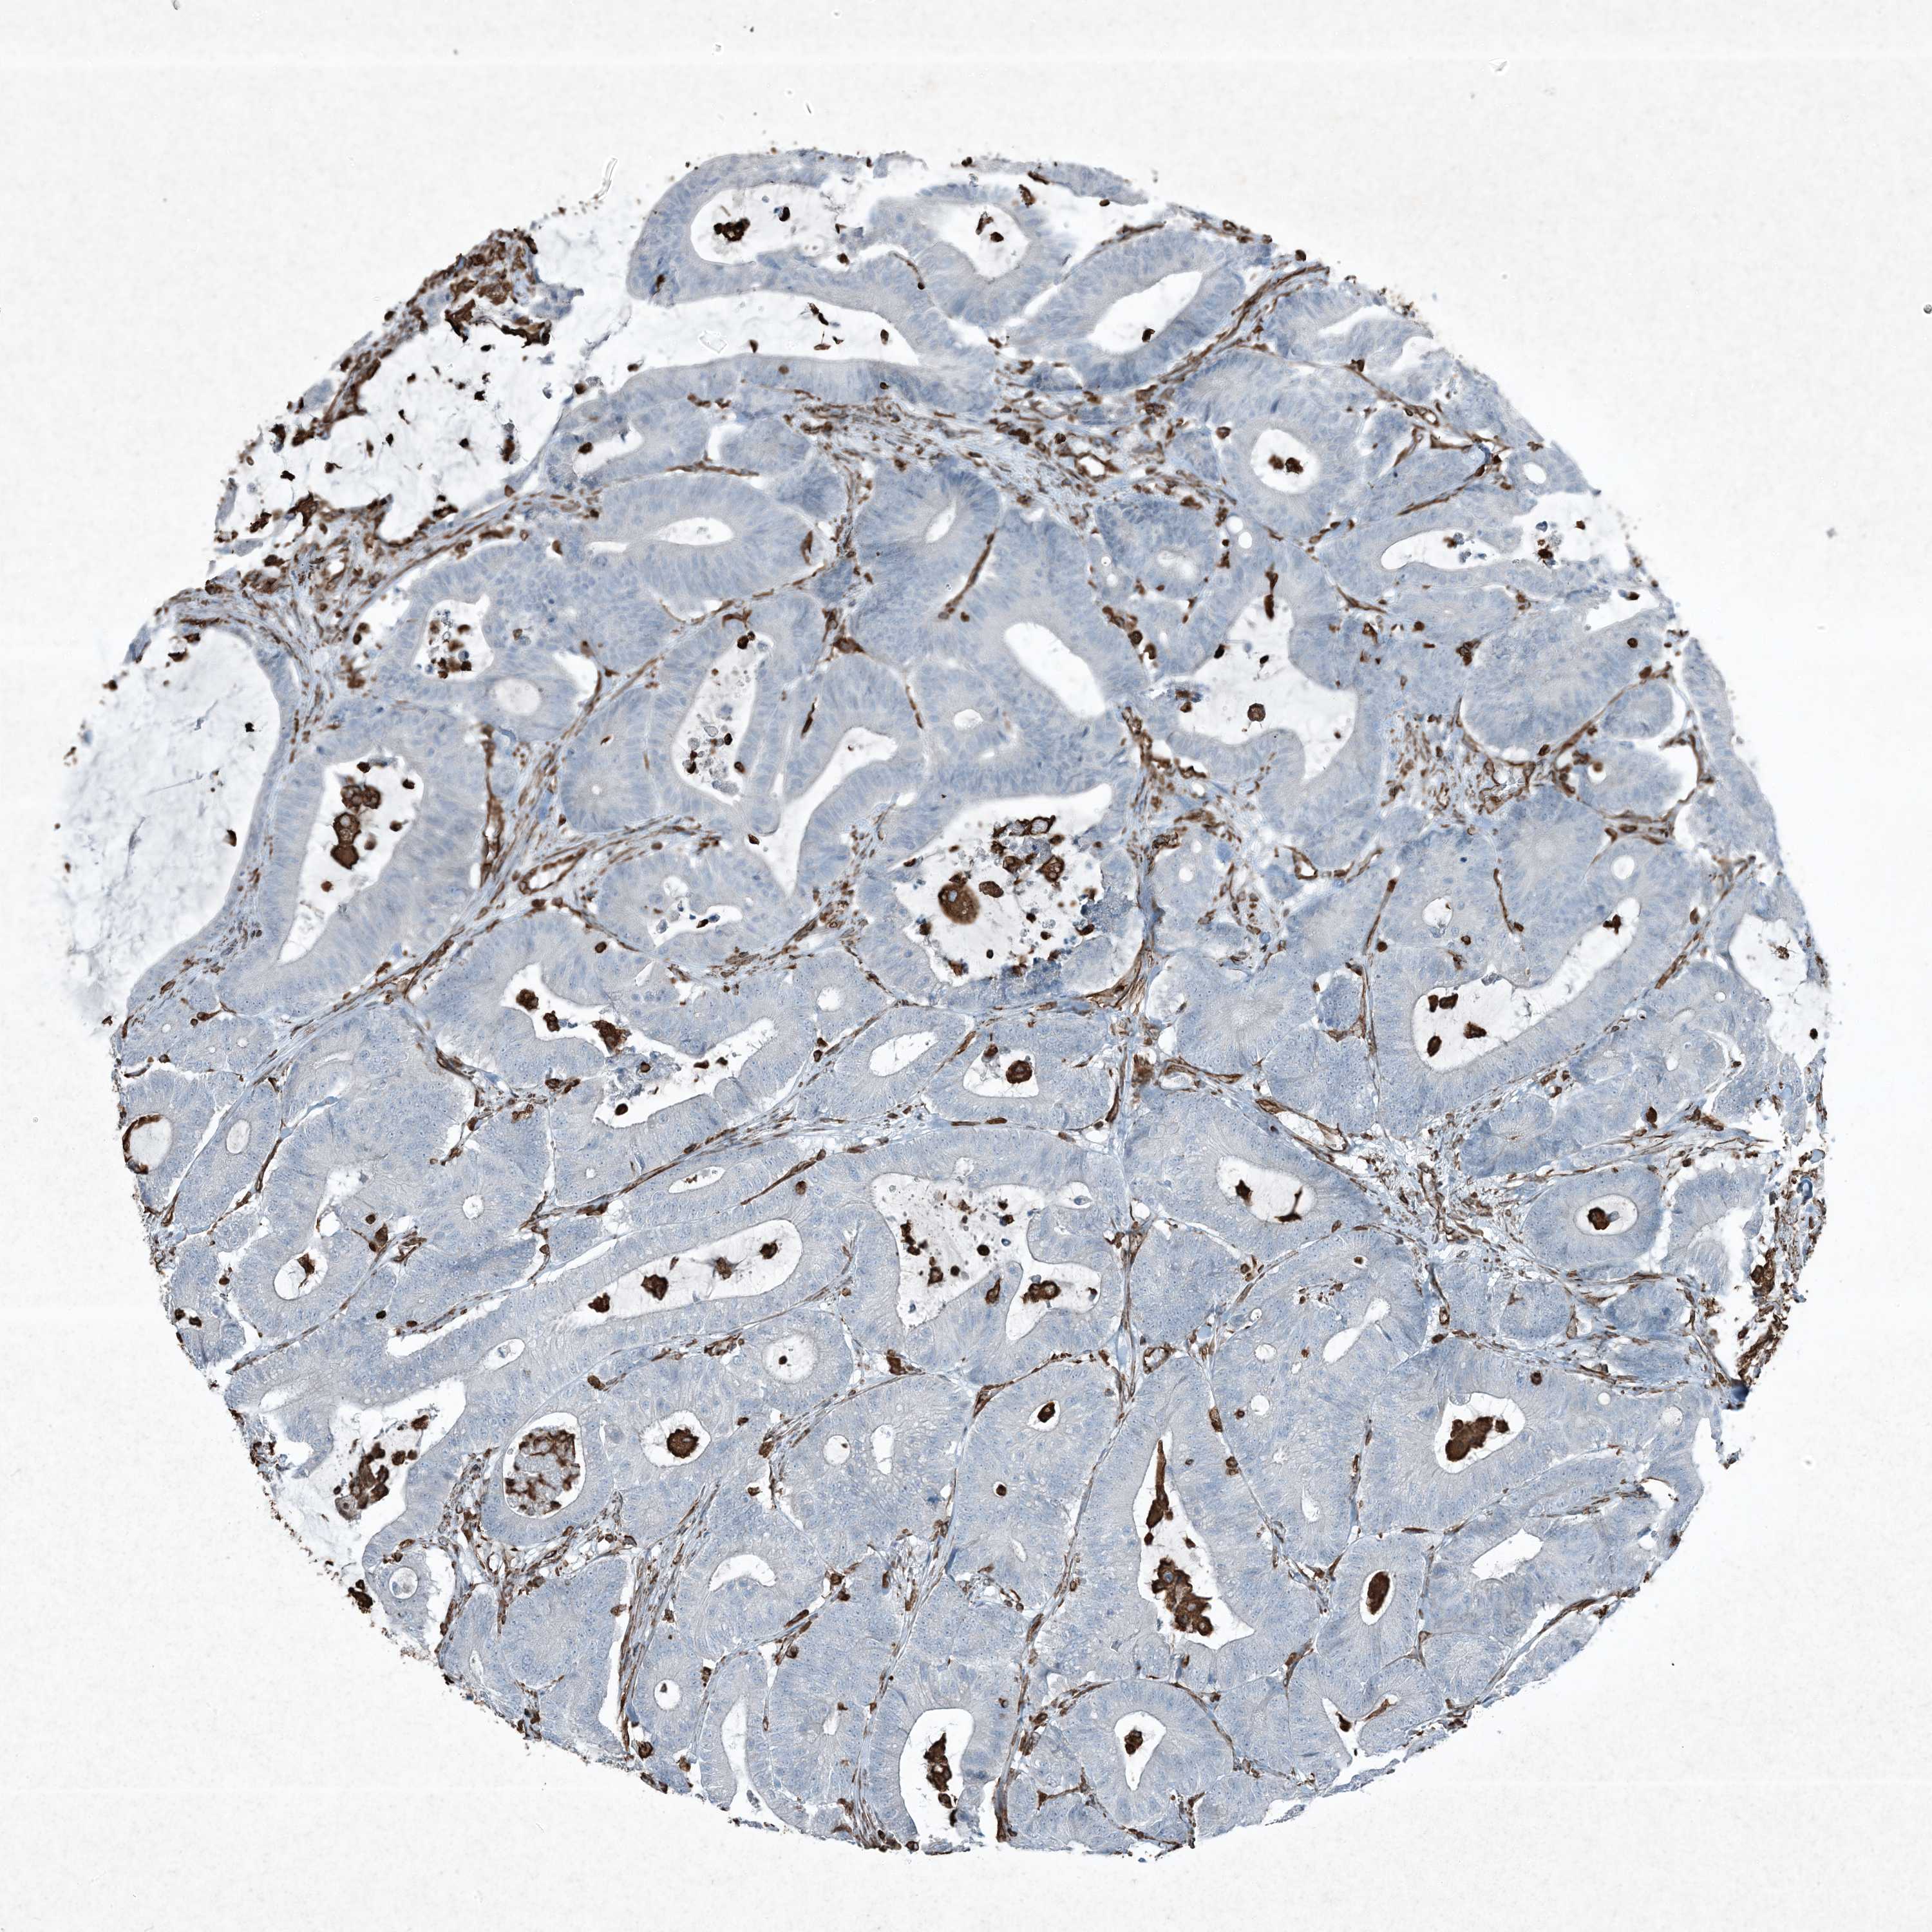

CANCER COLORECTAL CANCER Show tissue menu

Colorectal cancer

Human cancer

Colon adenocarcinoma